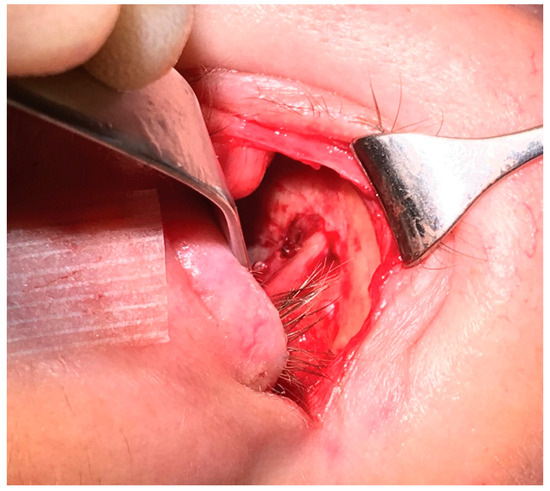

Case 5